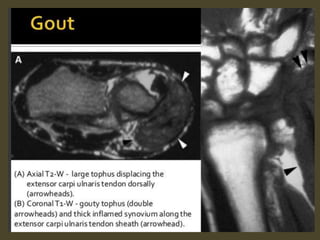

Tenosynovitis of Extensor Carpi Ulnaris.

Extensor carpi ulnaris tenosynovitis. Axial FS T2-WI shows fragmentation into multiple tendon fragments of

the extensor carpi ulnaris tendon (arrowheads). Note increased fluid and debris within the tendon sheath.